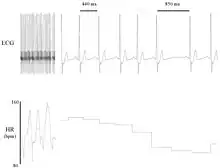

Heart rate variability (HRV) is the physiological phenomenon of variation in the time interval between heartbeats. It is measured by the variation in the beat-to-beat interval.

Other terms used include "cycle length variability", "R–R variability" (where R is a point corresponding to the peak of the QRS complex of the ECG wave; and R–R is the interval between successive Rs), and "heart period variability".[1] Measurement of the RR interval is used to derive heart rate variability.[1]

Variation in the beat-to-beat interval is a physiological phenomenon. The SA node receives several different inputs and the instantaneous heart rate or RR interval and its variation are the results of these inputs.[37] Contribution of the respiratory rhythm to sinus arrhythmia in normal unanesthetized subjects during mechanical hyperventilation with positive pressure.[37]